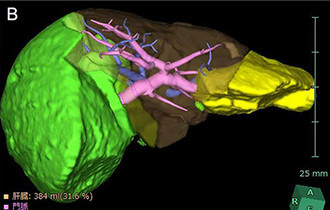

図2 VINCENTによるシミュレーション画像

肝臓や脈管の3次元的な描出が可能です。

肝臓の門脈がピンク色に、肝静脈が青色に、肝転移巣が緑色に描出されています (A)。

• シミュレーション画像:肝臓の門脈がピンク色に、肝静脈が青色に、肝転移巣が緑色に描出されている